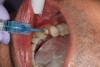

CAD/CAM dentistry is very precise. For accuracy, the preoperative, shade, bite, and upper/lower tooth scans are best taken before anesthesia and dental procedures that induce muscle fatigue (Figure 3). After infiltration anesthesia with 1 carpule of articaine hydrochloride 4% and epinephrine 1:100,000 injection, the temporary was removed. Occlusal reduction of 2.0 mm was precise and defined with an 828Y depth cutting bur to meet restorative requirements (Figure 4), and the post space was restored. Axial reduction and shoulder margination were performed with a coarse KS1 bur. After smoothing of the preparation, a 15% aluminum chloride topical gingival retraction paste was injected and compressed into the sulcus, then thoroughly rinsed with water and air-dried, before scanning of the tooth preparation and critical adjacent anatomy (Figure 5 and Figure 6).

Fig 4. Depth cutting allows precision reduction to avoid overreduction and compromise of restorative strength.

Figure 4